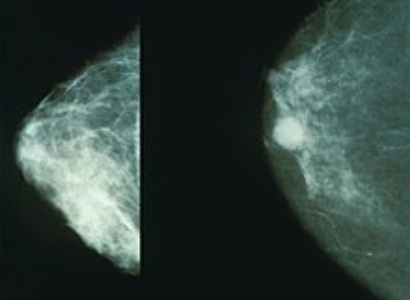

Las imágenes adjuntas al hilo ilustran este fenómeno de manera gráfica. En una mamografía normal (izquierda), el tejido mamario aparece denso y homogéneo, sin anomalías visibles. En la imagen contrastante (derecha), se observa una lesión nodular bien definida, un hallazgo que, según Corcos, podría representar un cáncer detectado precozmente… o uno inducido por el propio procedimiento.